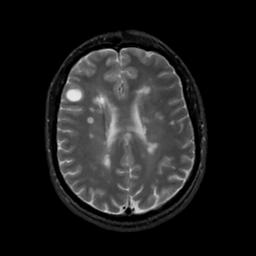

MR Study #3, February 24, 1991 -- Slice #32